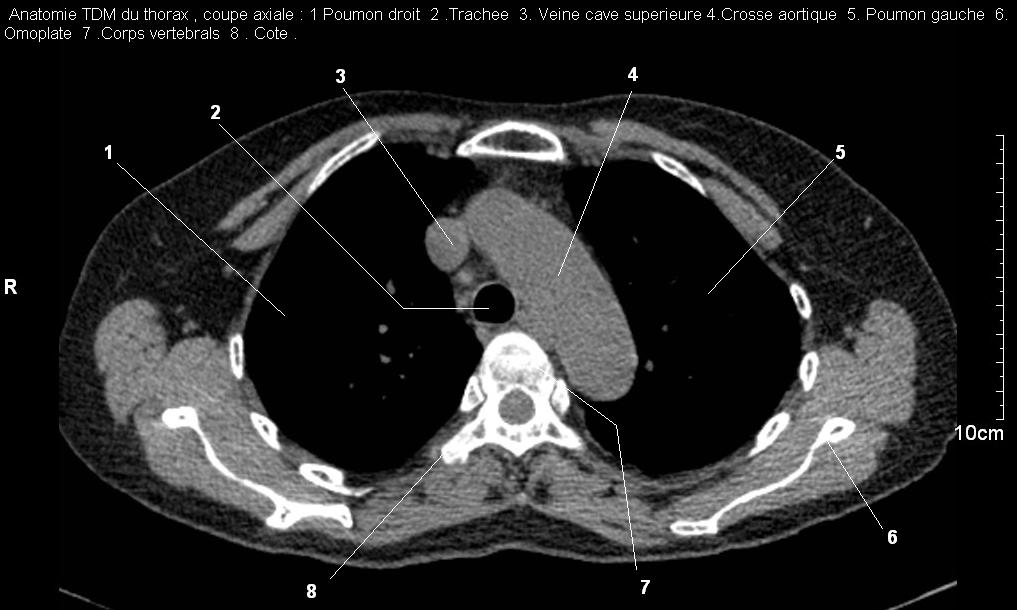

Radioanatomie TDM de l'abre tracheobronchique

fenetre mediastinal et fenêtre parenchymateuse :

Image

radiologique TDM normal coupe axiale , fenetre

mediastinale du trache . Le trache dans ce coupe est

en aspect de tube arrondie très hypodensite de vide

en avant pres de os vertebral TH3-4 . (

click pour entrer ) |